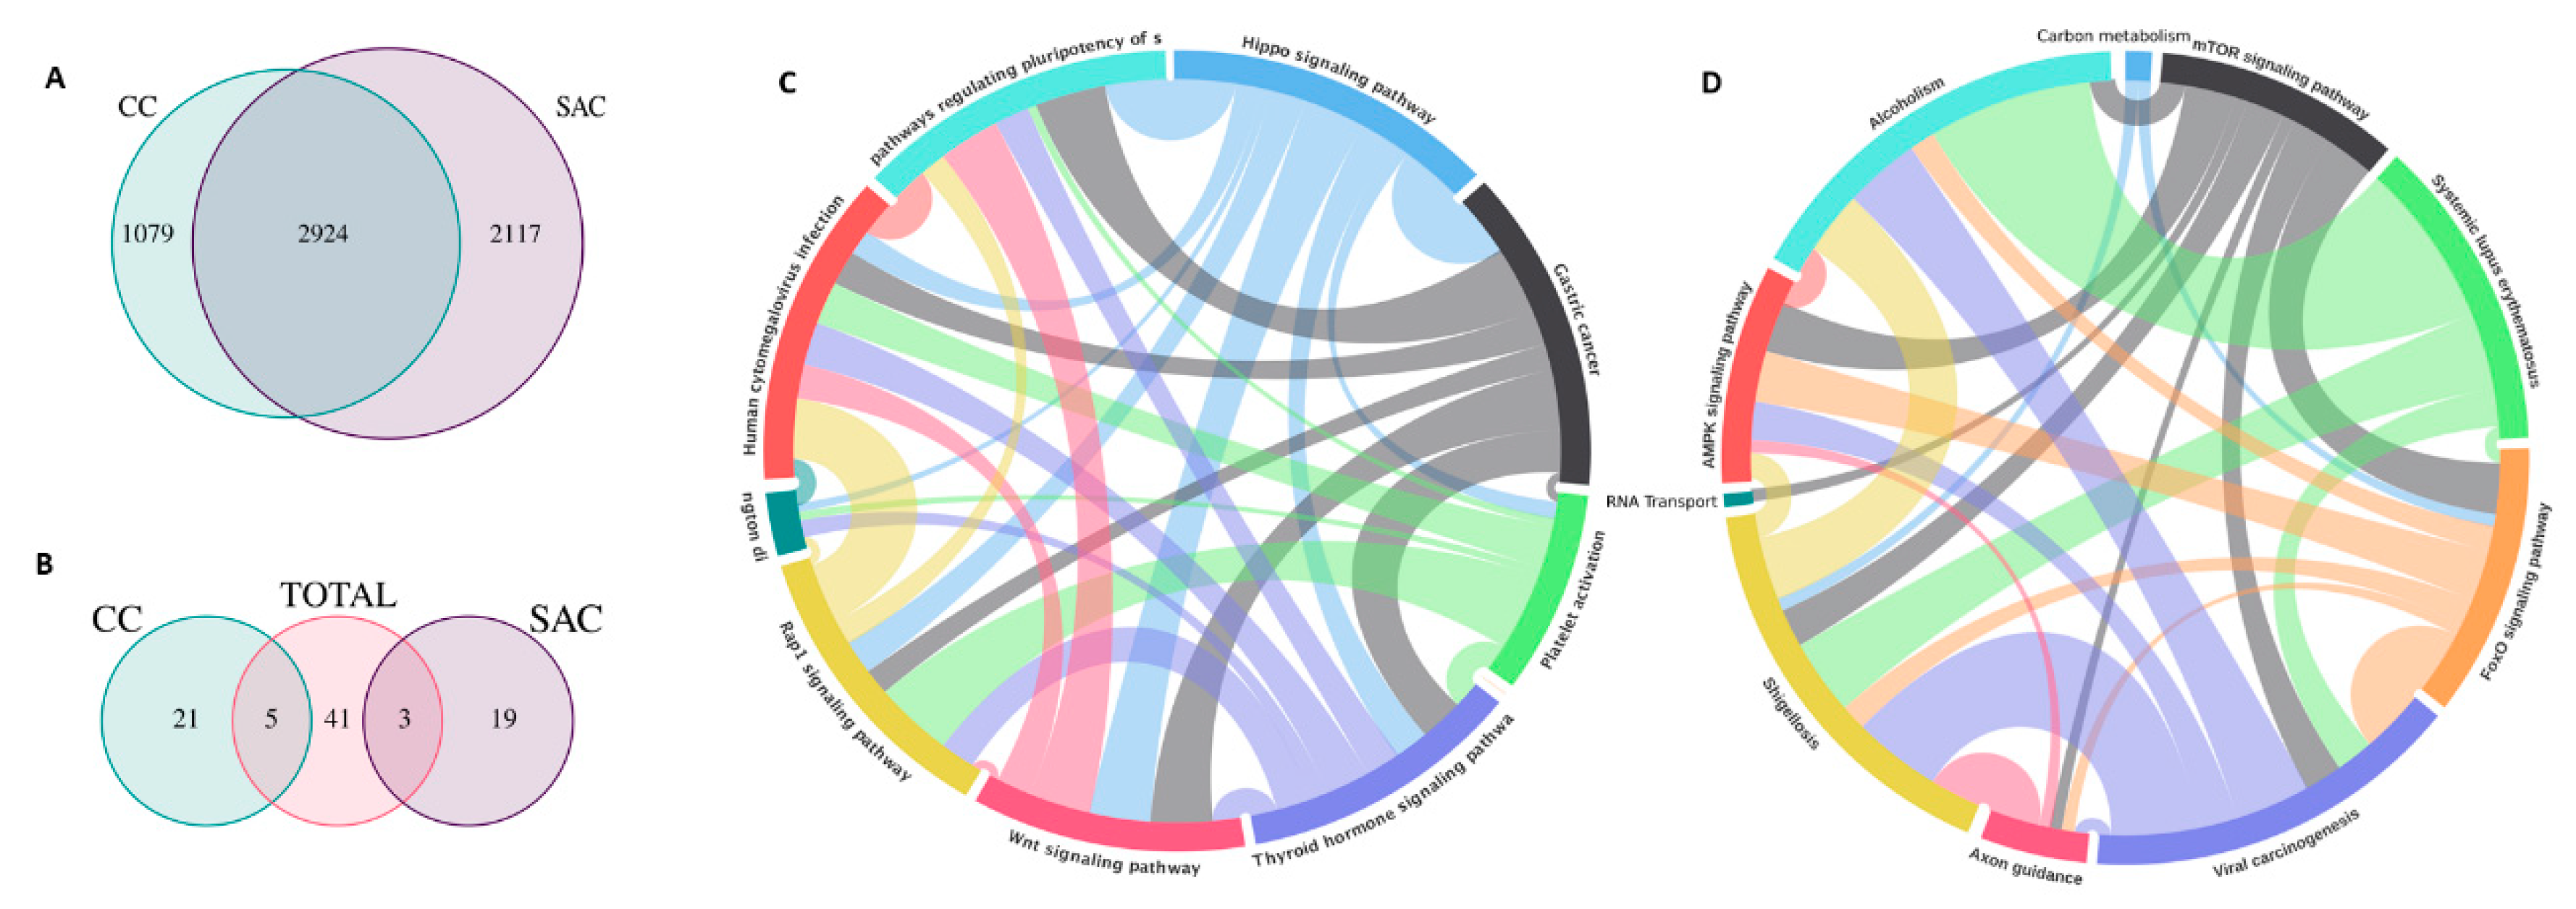

2. SAC Shows an Upregulation of Angiogenesis Markers

3. SAC is Especially Capable of Avoiding the Immune Response

4. SAC Displays an Active Invasive Front